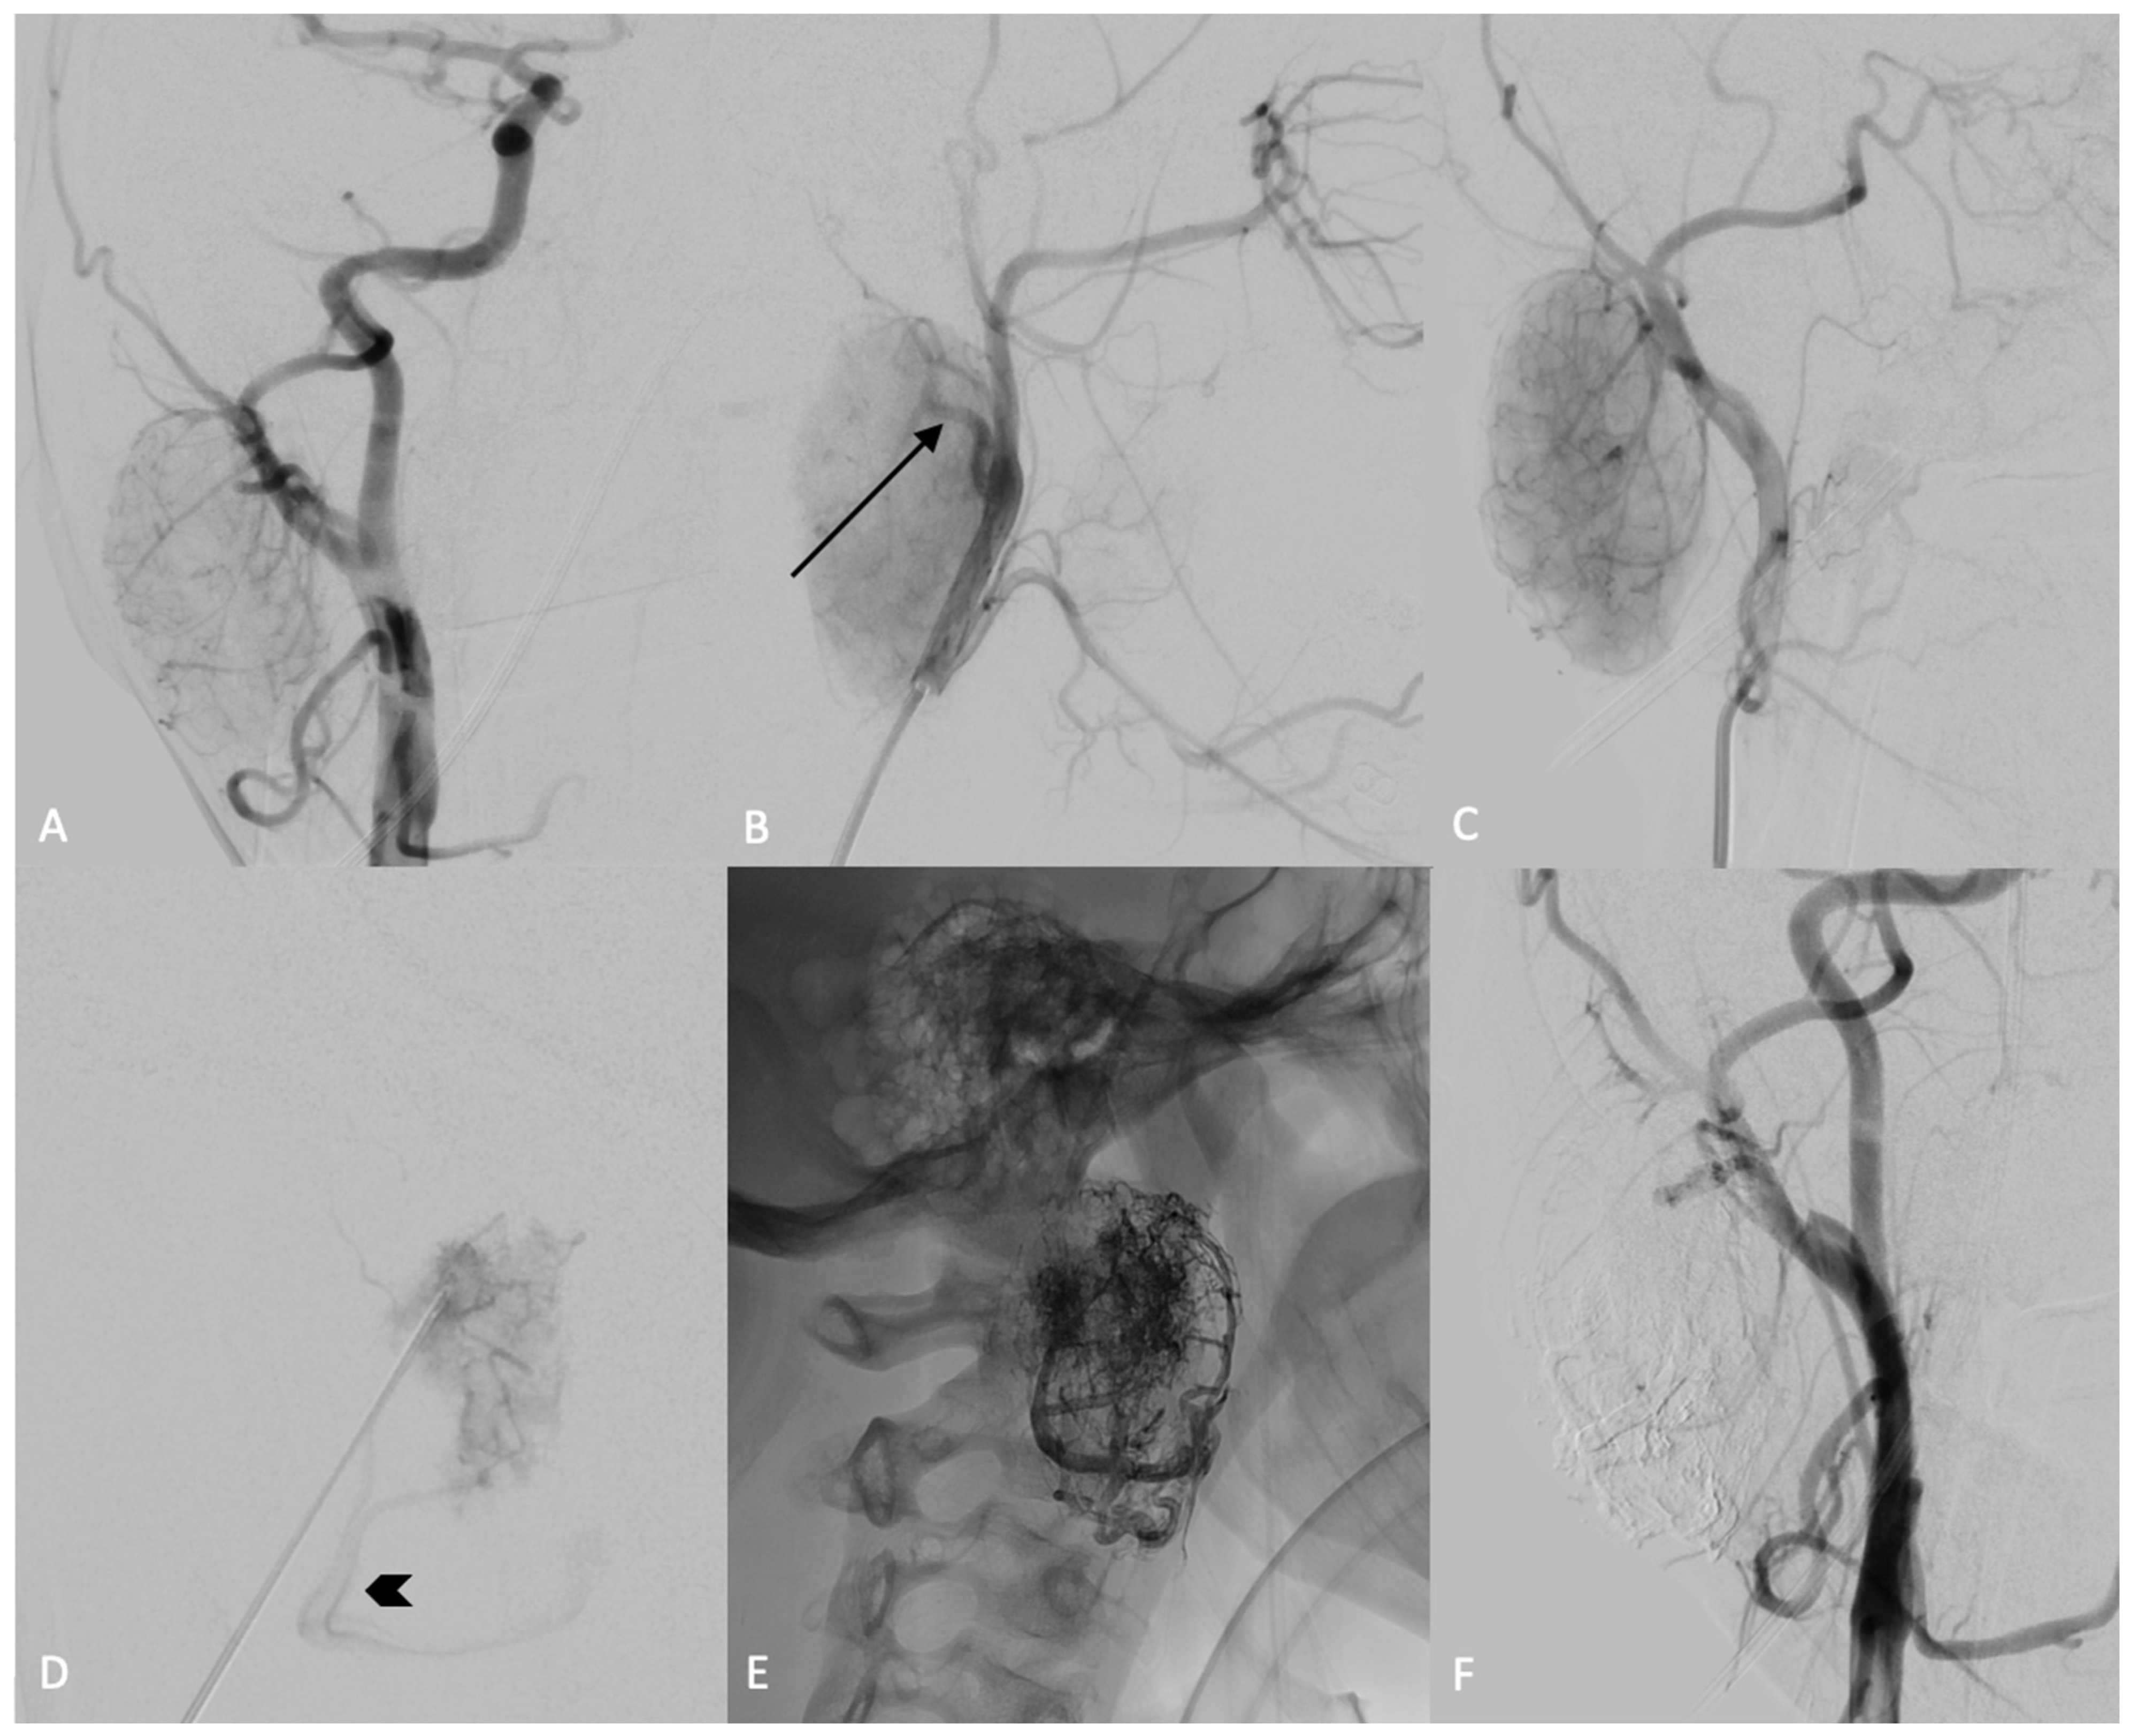

An MRI scan of the neck obtained approximately three months later revealed an oval hypervascular mass situated in the posterior region of the right parotid gland, positioned posteriorly to the common carotid bifurcation. This mass led to a medial displacement of the internal and external carotid arteries (Figure 1).

Figure 1. Axial T2WI (A), T2WI (B) and T1WI after contrast medium (C) demonstrate a well-defined solid lesion within the right parotid gland, which is hypo-intense on T1WI, relatively hyperintense in the T2WI image and hyper-intense on T1WI with contrast. There is only a mild diffusion restriction on DWI (E) and ADC maps (F). On coronal suppressed T2WI (D), and on axial T2WI (A), we observe some flow-voids images, with expression of high-flow blood vessels, confirmed on T1WI after contrast medium (C). Technique: 1.5T MR scanner. 3.0 mm slice thickness.